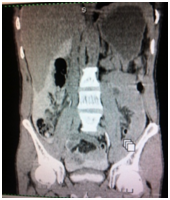

Diagnostic and treatment processes of patients was carried out according to the diagnostic algorithm developed in the Republican research center for emergency medicine at injury of a bladder taking into account the dominating pathology. On this diagnostic algorithm taken patent from Agency on intellectual property of the Republic of Uzbekistan. No. DGU 2010 0177. The valuable diagnostic method of bladder injury is retrograde cystography. At doubtful cases CT more precisely allows to determine the volume and nature of bladder injury and to estimate condition of other associated lesions. At 5 (4.2%) patients the isolated injury of a bladder managed by laparoscopic repair of a bladder rupture on an urethral catheter (Figures 1 & 2).

Figure 1 Retrograde CT cystogram. Bladder filled with contrast. Extravasation of contrast.